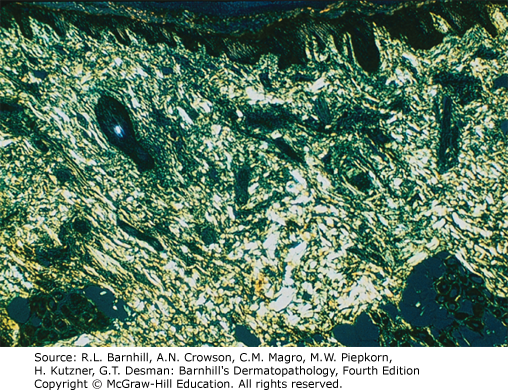

Differentiating between the different types of amyloid is important clinically and for test-taking purposes. Amyloidosis can be divided into systemic primary, systemic secondary, and localized. Genetic and hemodialysis-associated forms also exist. There are three main forms of localized cutaneous amyloidosis: macular, lichen, and nodular amyloidosis. Amyloid has green birefringence with polarized light when stained with Congo red as shown below.

Nodular amyloidosis presents clinically with brown-pink papules or nodules typically on the lower extremities/acral surfaces and the face. Histologically, amyloid deposits are found in the dermis, can extend into the subcutis, and are frequently found within vessel walls. Nodular amyloidosis is differentiated from the other two forms of localized cutaneous amyloidosis by the presence of AL protein derived from immunoglobulin light chains. Nodular amyloidosis has an approximately 7% risk of progression to systemic amyloidosis; therefore, these patients should be monitored closely. Additionally, nodular amyloidosis can be associated with autoimmune conditions, particularly Sjogren's syndrome, and patients should be screened accordingly.